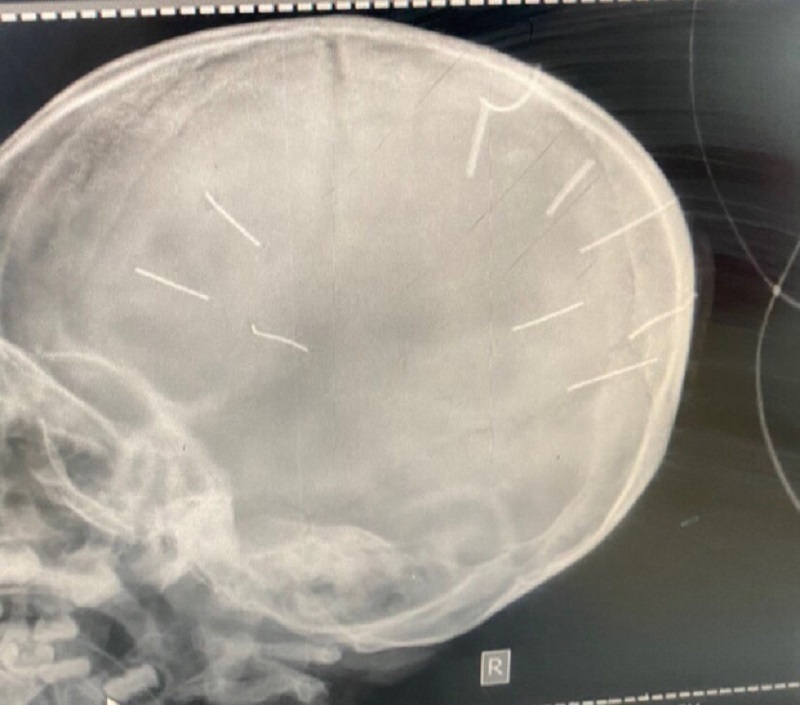

Hình chụp cắt lớp phát hiện hình ảnh giống đinh trong sọ cháu bé.

Rạng sáng 18/1, bé A. đã được chuyển đến Bệnh viện đa khoa Xanh Pôn. Bệnh viện đã tiến hành chụp cắt lớp, nhận thấy có những hình ảnh như những chiếc đinh và tiên lượng sức khỏe của bé A đang nguy kịch.